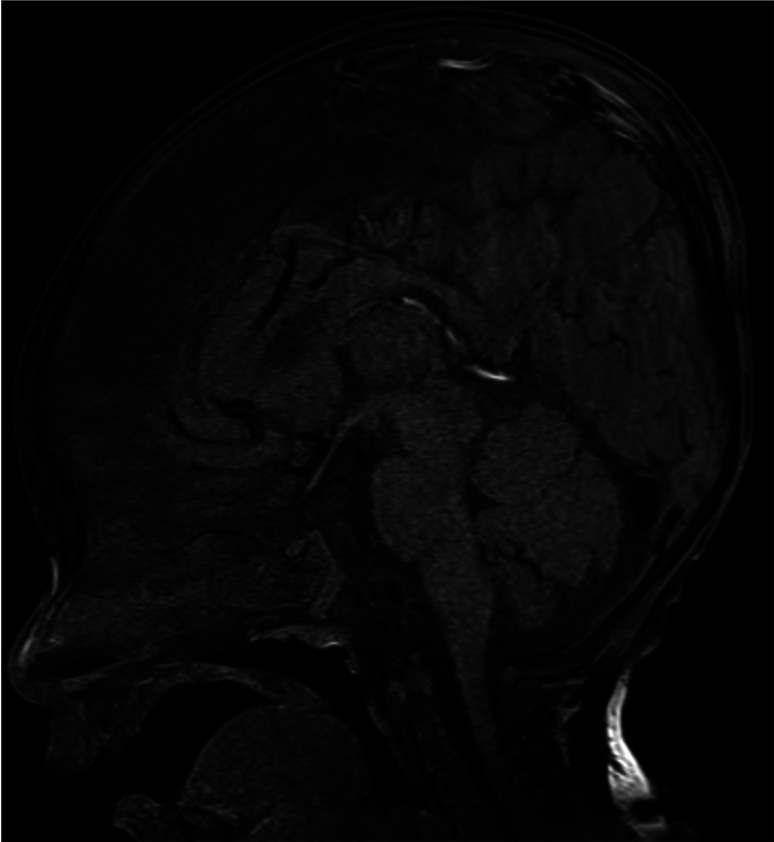

Transient central diabetes insipidus after cranioplasty for craniosynostosis in an infant with septo-optic dysplasia.